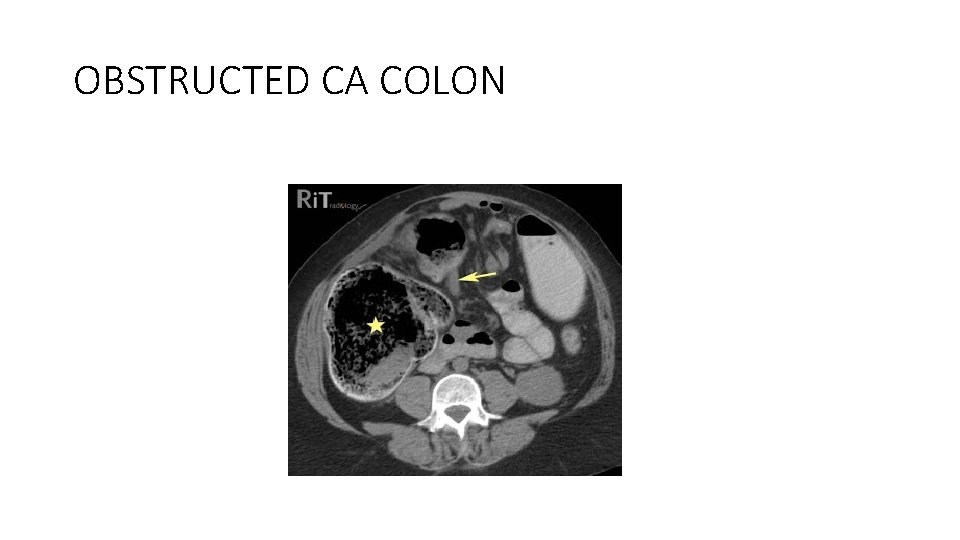

Computed tomography • CT scanning is the imaging of choice if a colonic obstruction is clinically suspected. • Contrast-enhanced CT (PO and IV) can help to delineate between partial and complete obstruction, ileus, and small-bowel obstruction. • water-soluble contrast should be used preferentially

OBSTRUCTED CA COLON

Left colon carcinoma • Surgical treatment of left colon carcinoma includes 1. resection without primary anastomosis 2. resection with primary anastomosis and intraoperative lavage • Endoscopically placed expandable metal stents can be used to relieve the large-bowel obstruction, thus allowing for a primary colorectal anastomosis